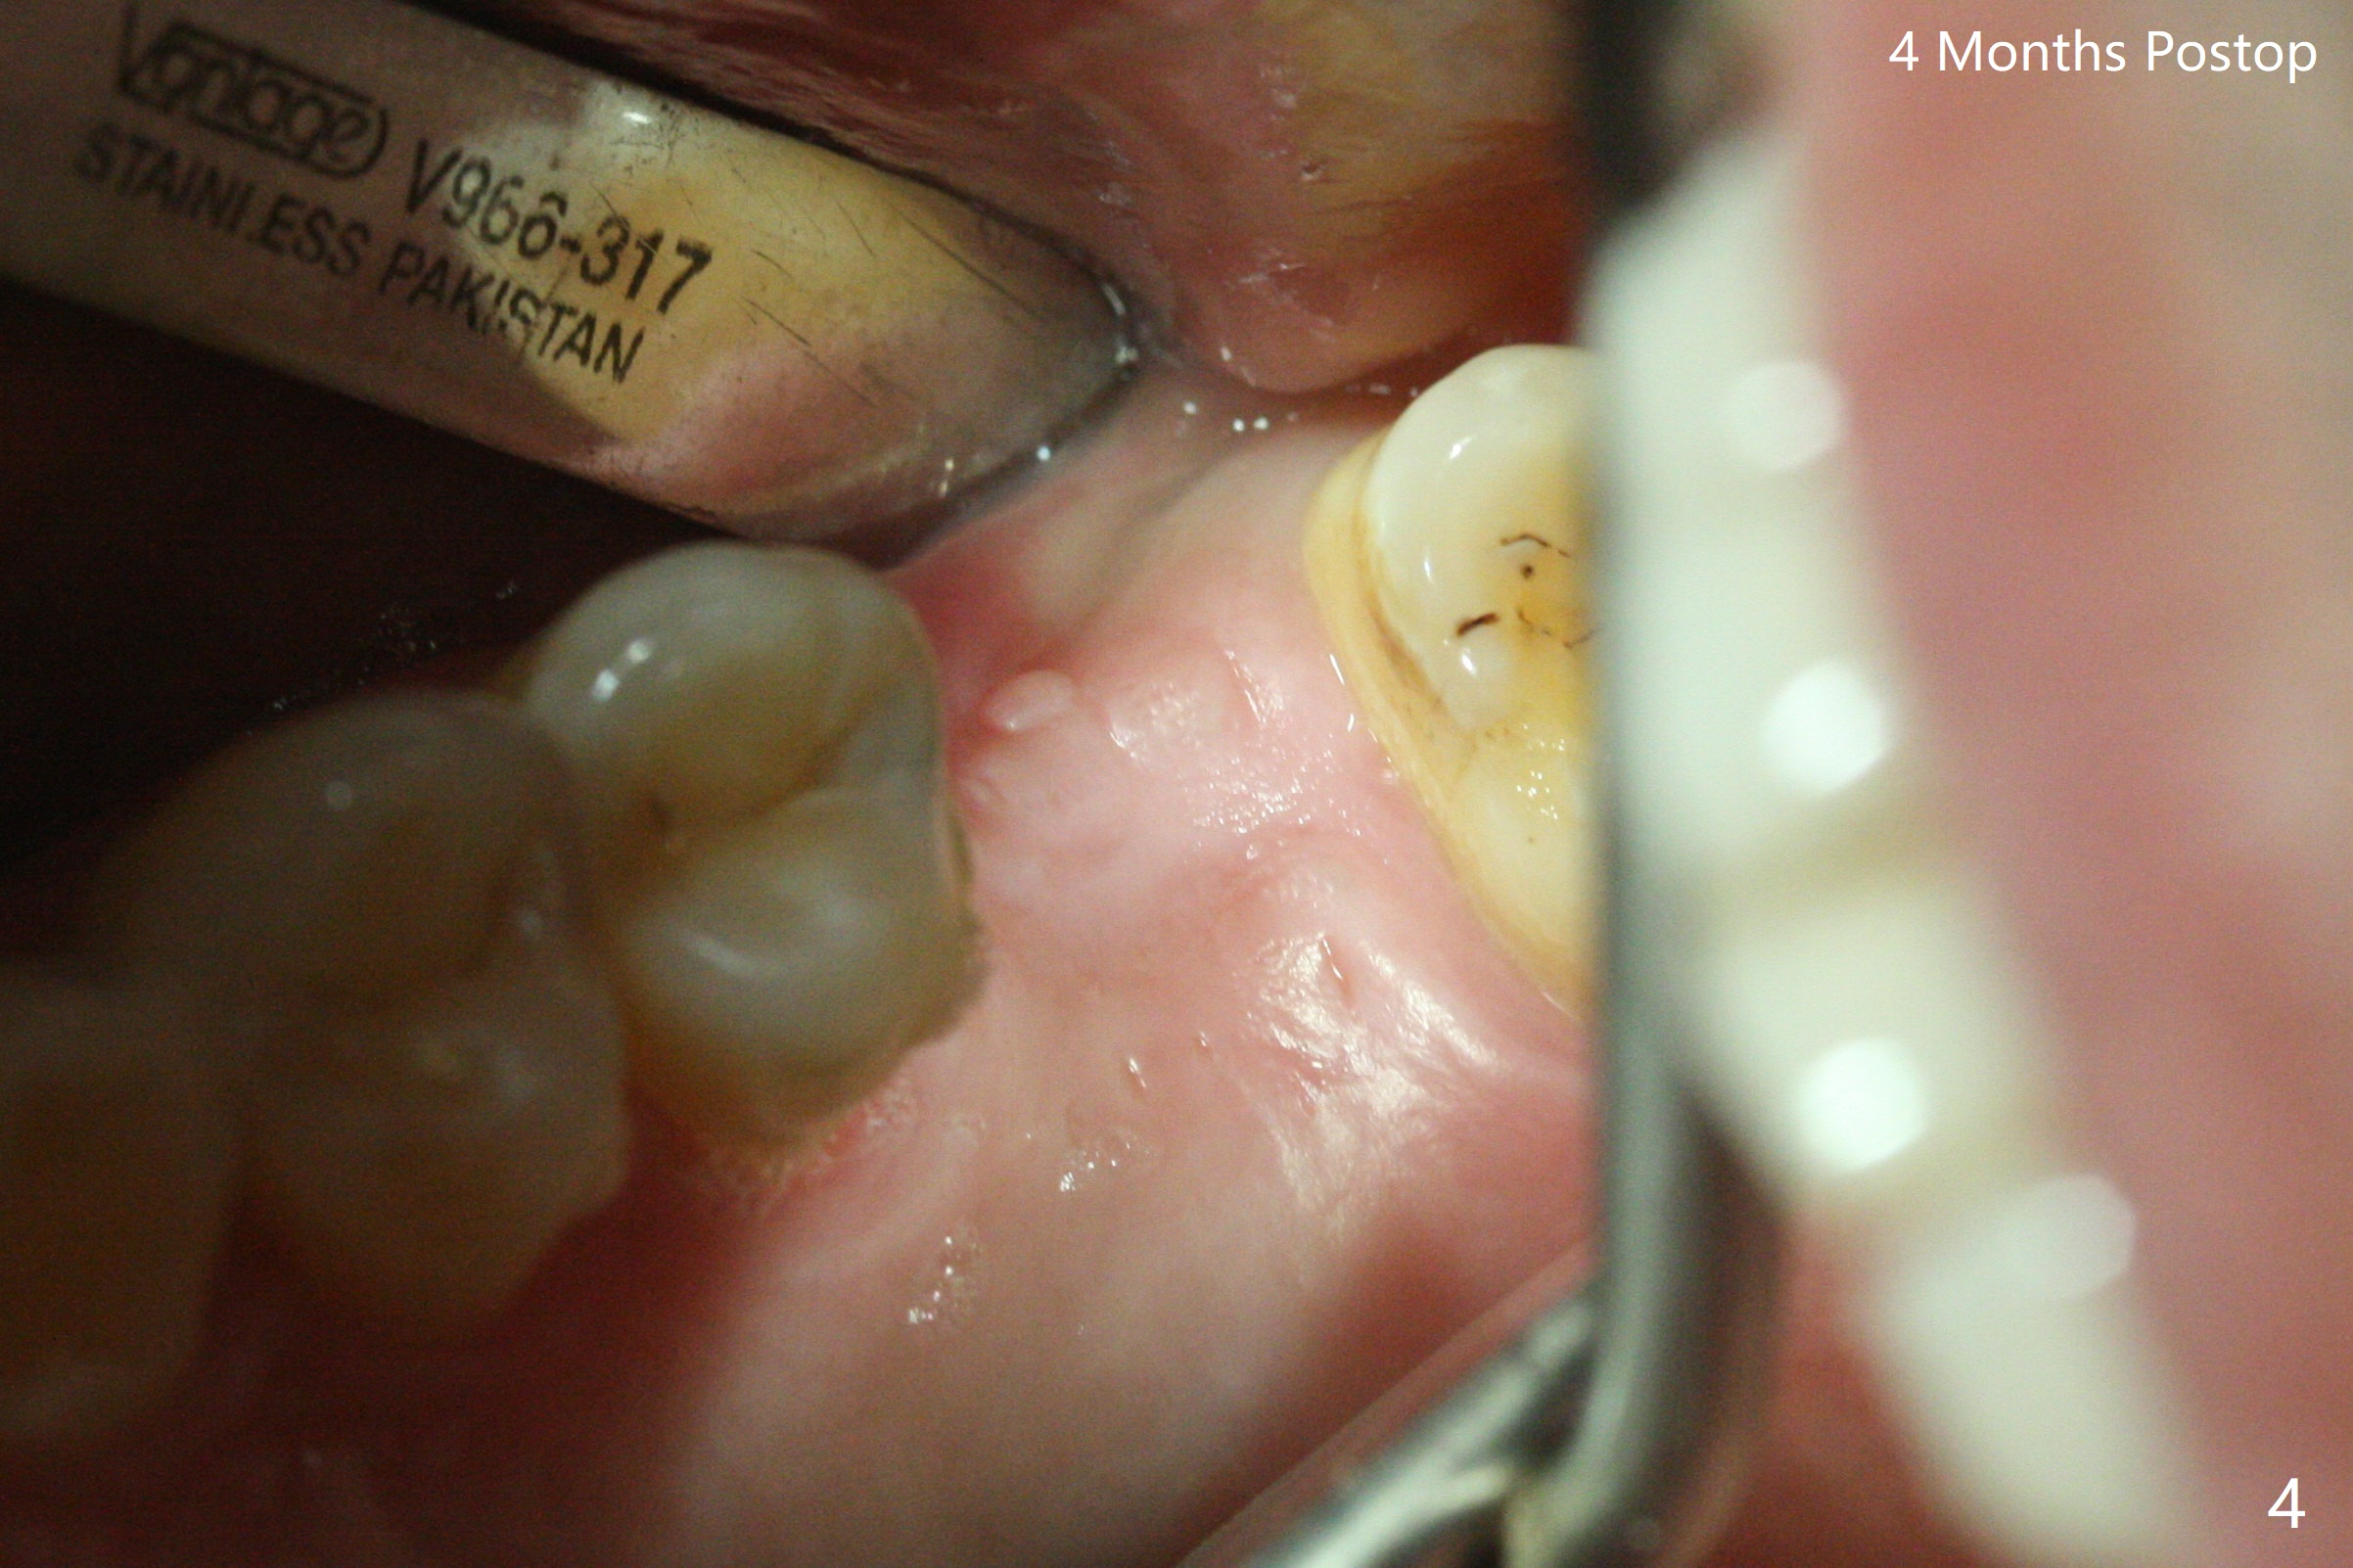

When the crown and abutment at #14 are removed, the implant is found to be shallowly placed. Upon incision, the implant threads are exposed circumferentially and coronal to the buccal crest (Fig.1 *). It seems to be difficult to expect bone regeneration post bone graft. The implant (6.4x6 mm) is removed with a 7/8 mm trephine bur, followed by sticky allograft (Fig.2 *), PRF membrane and 6-month membrane. In spite of the setback, the bone height increases from 3.9 mm to 11 mm due to sinus lift associated with the previous implant placement (Fig.2 L). The depth of the 2nd placement will be controlled by surgical guide. When the periodontal dressing dislodges 11 days postop, the 6-month membrane is lost as well as part of the bone graft. If there is remaining apical native bone, an immediate implant should be placed so that bone graft can be kept in place more securely with an immediate abutment and provisional! The seemingly conservative approach is actually not safe. The wound heals 1 month postop (following dislodgement of the 2nd periodontal dressing, Fig.3). Three months later, consider using bone expanders to do sinus lift and place a SM implant subcrestal. Take PA after 1st expander to the depth. The wound heals 4 months postop (Fig.4), but the bone height (Fig.5) and width (Fig.6) decreases. The latter continues to decrease 9 months postop (Fig.7,8), but bone density is high, average 1360 units. Preparation includes guide, incision, sinus lift, implant placement (possibly tissue-level (9) or FC if the sinus membrane perforates), bone graft, and suture.